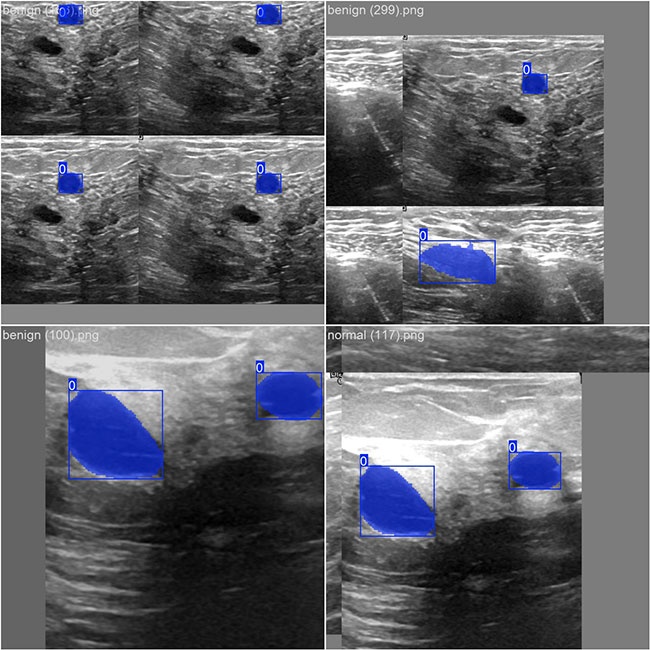

部分数据集图像如下图所示:

部分标注如下图所示:

本研究采用了乳腺癌相关超声影像数据集作为研究基础,并通过Labelme工具对图像中的分割标记及其分类信息进行了精确标注。在此数据集基础上应用YOLOv8n模型进行训练操作,并从性能指标角度全面评估并对比分析了模型在验证集的表现情况。整个训练与评估流程主要包括以下几个步骤:首先是数据预处理阶段的数据准备工作;其次是基于所选模型架构展开的具体训练过程;最后是对训练完成后模型性能的关键指标进行系统性检验与结果对比分析。研究目标类别主要集中在乳腺癌肿瘤相关超声影像这一领域范畴内。所涉数据总量共计780张图像,在具体分布上可分为以下几类:乳腺癌肿瘤相关超声影像约占比65%,甲状腺功能亢进症相关超声影像占比约25%,其余类型仅占约10%的比例范围。